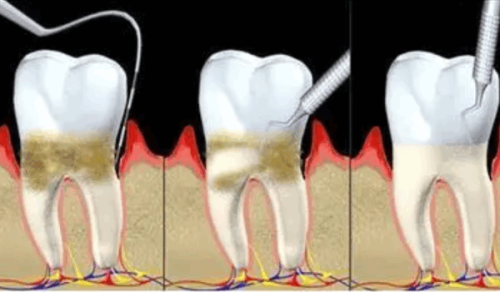

健康层面:矫正的核心价值远不止美观,更在于对口腔健康的深层维护。通过调整咬合关系,能减少牙齿磨损、食物嵌塞问题,从根源上降低牙周炎、龋齿的发病风险;同时,优化后的咀嚼功能能提升食物的研磨效率,助力消化系统正常运作,减少肠胃负担。30岁后牙齿问题若放任不管,会随年龄增长加重健康隐患,而矫正能提前规避这类风险,为中老年口腔健康打下基础。